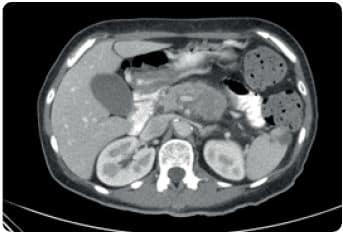

TAC toracoabdominopélvico: masa localizada en cuerpo y cola pancreática compatible con neoplasia con probable afectación vascular. Lesión focal hepática de 6 mm indeterminada con este estudio, sin poder descartar afectación secundaria. Imagen hipodensa de morfología triangular sugestiva de infarto esplénico.

Adenopatía retroperitoneal para aórtica izquierda única (9 mm de eje menor). RMN hepática: Lesión focal hepática en segmento 4 que por su intensidad de señal y comportamiento en el estudio dinámico es sugestiva de depósito secundario.

ECOENDOSCOPÍA ALTA: Lesión en cuerpo de páncreas hipoecogénica sólida de contornos irregulares (35 x 41 mm) de aspecto maligno. Compromiso vascular del tronco celíaco y arteria mesentérica superior (uT4). BIOPSIA: Adenocarcinoma de páncreas.

Ver imagen a la derecha.